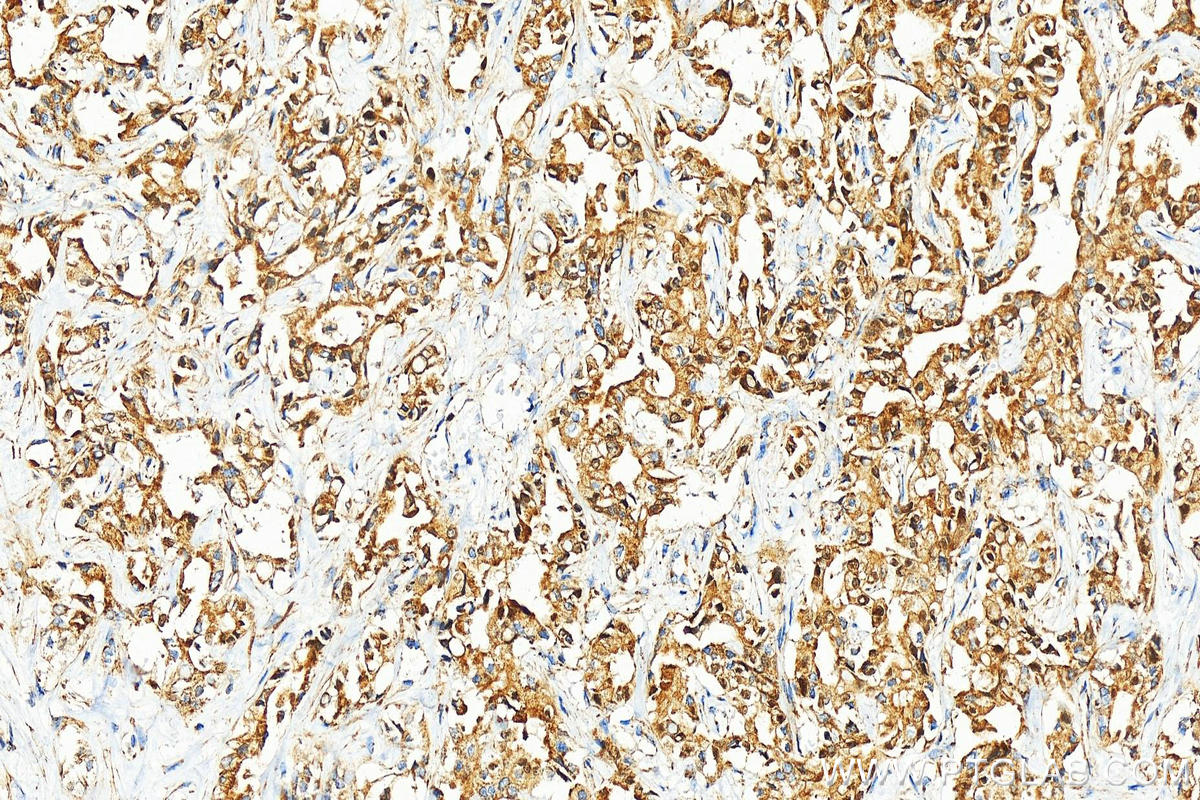

| Positive IHC detected in | human intrahepatic cholangiocarcinoma tissue, human stomach cancer tissue, rat kidney tissue Note: suggested antigen retrieval with TE buffer pH 9.0; (*) Alternatively, antigen retrieval may be performed with citrate buffer pH 6.0 |

| Immunohistochemistry (IHC) | IHC : 1:200-1:800 |